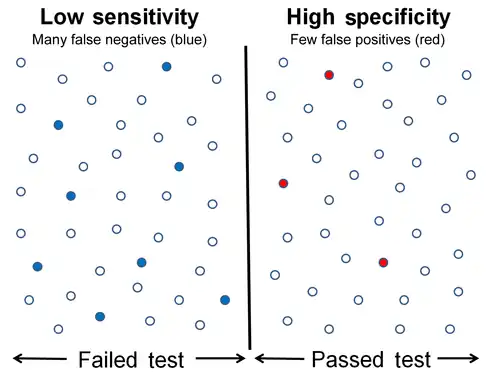

Graphical illustration

-

A graphical illustration of sensitivity and specificity

A graphical illustration of sensitivity and specificity

The above graphical illustration is meant to show the relationship between sensitivity and specificity. The black, dotted line in the center of the graph is where the sensitivity and specificity are the same. As one moves to the left of the black dotted line, the sensitivity increases, reaching its maximum value of 100% at line A, and the specificity decreases. The sensitivity at line A is 100% because at that point there are zero false negatives, meaning that all the negative test results are true negatives. When moving to the right, the opposite applies, the specificity increases until it reaches the B line and becomes 100% and the sensitivity decreases. The specificity at line B is 100% because the number of false positives is zero at that line, meaning all the positive test results are true positives.

-

High sensitivity and low specificity

High sensitivity and low specificity -

Low sensitivity and high specificity

Low sensitivity and high specificity

The middle solid line in both figures above that show the level of sensitivity and specificity is the test cutoff point. As previously described, moving this line results in a trade-off between the level of sensitivity and specificity. The left-hand side of this line contains the data points that tests below the cut off point and are considered negative (the blue dots indicate the False Negatives (FN), the white dots True Negatives (TN)). The right-hand side of the line shows the data points that tests above the cut off point and are considered positive (red dots indicate False Positives (FP)). Each side contains 40 data points.

For the figure that shows high sensitivity and low specificity, there are 3 FN and 8 FP. Using the fact that positive results = true positives (TP) + FP, we get TP = positive results - FP, or TP = 40 - 8 = 32. The number of sick people in the data set is equal to TP + FN, or 32 + 3 = 35. The sensitivity is therefore 32 / 35 = 91.4%. Using the same method, we get TN = 40 - 3 = 37, and the number of healthy people 37 + 8 = 45, which results in a specificity of 37 / 45 = 82.2 %.

For the figure that shows low sensitivity and high specificity, there are 8 FN and 3 FP. Using the same method as the previous figure, we get TP = 40 - 3 = 37. The number of sick people is 37 + 8 = 45, which gives a sensitivity of 37 / 45 = 82.2 %. There are 40 - 8 = 32 TN. The specificity therefore comes out to 32 / 35 = 91.4%.